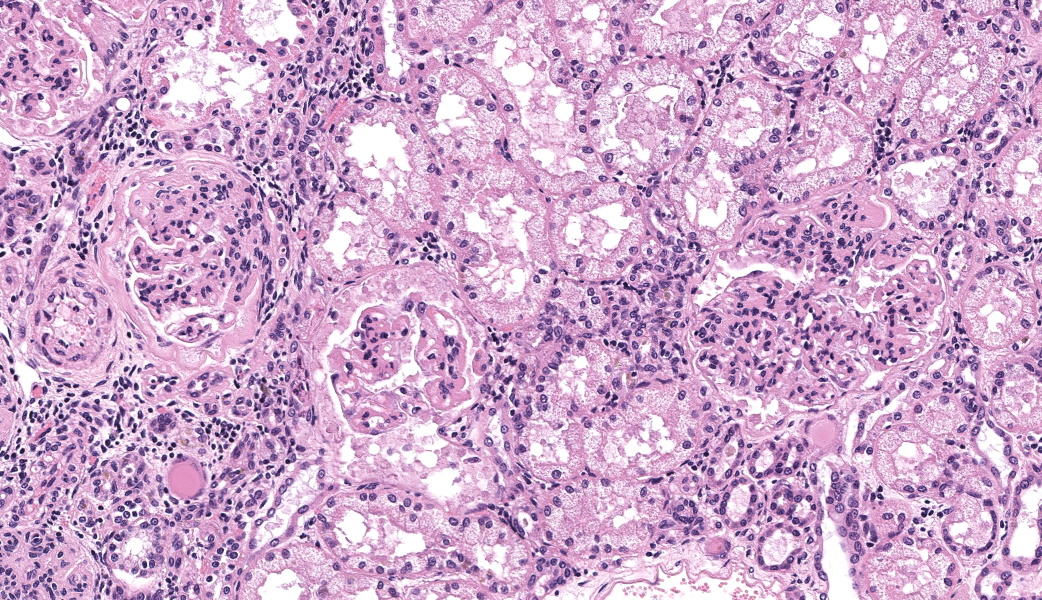

There are multiple sections of kidney that include cortex, medulla, and papilla. All of the glomeruli are affected to varying degrees of severity. The glomeruli are globally hypercellular, within both the endocapillary and mesangial compartments. Capillary walls are markedly thickened by eosinophilic matrix. There is frequent dilation of Bowman’s capsules and segmental collapsed glomerular tufts/ capillaries with expansion of mesangium with eosinophilic matrix (segmental sclerosis). Less than 25% of the glomeruli are globally sclerotic. Occasionally glomerular tufts are segmentally to globally effaced by eosinophilic mesangial matrix, and mesangial and intracapillary dark brown (hemosiderin) and yellow (hematoidin) pigment with scattered hemosiderin laden macrophages within Bowman’s space. There is infrequent segmental loss of podocytes with proliferation of eosinophilic matrix and cells that adhere the glomerular tuft to Bowman’s capsule (crescents). Several glomerular capillary loops are filled with fibrin thrombi.Over half of the tubules are characterized by attenuated epithelium, sloughed hypereosinophilic necrotic intraluminal epithelium, and/or piling of basophilic tubular epithelium (regeneration). Often tubules are dilated with eosinophilic proteinaceous material (hyaline casts), and contain intraluminal basophilic refractile material (mineralization). Infrequently, tubules are filled with degenerate neutrophils. There is a mild loss of tubules with expansion of the interstitium by fibrous matrix and aggregates of lymphocytes with fewer plasma cells. There are multiple arcuate arteries with an expanded tunica intima by increased numbers of smooth muscle cells and fibrous matrix, and/or thickened and hypercellular tunica medias (arteriosclerosis).

Special stains included Masson’s Trichrome, Periodic-Acid Schiff (PAS), and Jones Methenamine Silver (JMS). The PAS demonstrated that the thickened mesangium and glomerular capillary loops were expanded by PAS positive material that often-formed double contours, spike-like projections and encircled bright magenta deposits using the Trichrome stain. Both the PAS and Trichrome highlight the collapsed capillary loops of the globally sclerotic glomeruli with expansion of Trichrome and PAS positive matrix.

Closing out our fourth conference, this case graced participants with an opportunity to see a lovely correlation between light microscopy and electron microscopy (EM) findings. It’s not often that EM images are sent in as part of Wednesday Slide Conference submissions, but it’s always a treat when they are! Many thanks to the contributor for providing both a wonderful slide and beautiful EM images. Together, they truly did paint the whole picture for this EM-worthy condition.Because the EM images were provided, a review of the ultrastructural anatomy of a glomerular capillary profile and its surrounding structures ensued, with focus on the primary and secondary foot processes of the visible podocyte and the different layers of the glomerulus. However, the main show was the electron-dense, granular, irregularly shaped clumps of immune complexes (IC) within subepithelial, intramembranous, and subendothelial spaces of the glomerular tuft. Having IC deposition demonstrably in all three of those locations within the glomerulus assisted with the determination of the “mixed” type of glomerulonephritis in this case. Conference participants favored “membranoproliferative” based on the H&E slide, but acknowledged that this case did not fit 100% into that box upon review of the EM images and accepted the use of the term “mixed” in discussion. Typing of glomerulonephritis is more difficult to do with light microscopy alone due to some histologic similarities between the types, bringing home the point that, for definitive characterization of glomerulonephritis, EM is indispensable.

There was discourse on differentiating membranoproliferative from membranous glomerulonephritis based on histologic features, as some conference participants went one way or the other in their morphologic diagnoses. To summarize, membranoproliferative glomerulonephritis will have an increased number of nuclei within the glomerular tuft, mesangial cell proliferation, and often, the presence of recruited neutrophils. Membranous glomerulonephritis typically just has an increased amount (thickening) of basement membranes. One conference participant inquired on the histologic differences between synechiae and crescents in the glomerulus. Synechiae were described as the touching of the visceral layer of Bowman’s capsule to the parietal layer without fibrosis, whereas crescents have a fibrous component and demonstrate full adhesion of the glomerulus to the capsule. Conference participants did not think there was enough histologic evidence of thrombotic microangiopathy include it in the morphologic diagnosis in this particular case.